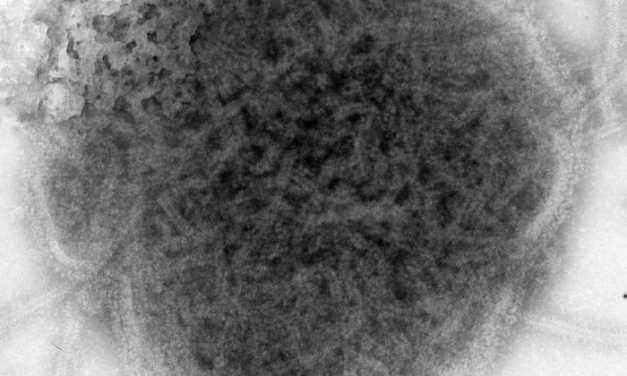

Die Masern sind eine durch das Masernvirus hervorgerufene, hoch ansteckende Infektionskrankheit,...